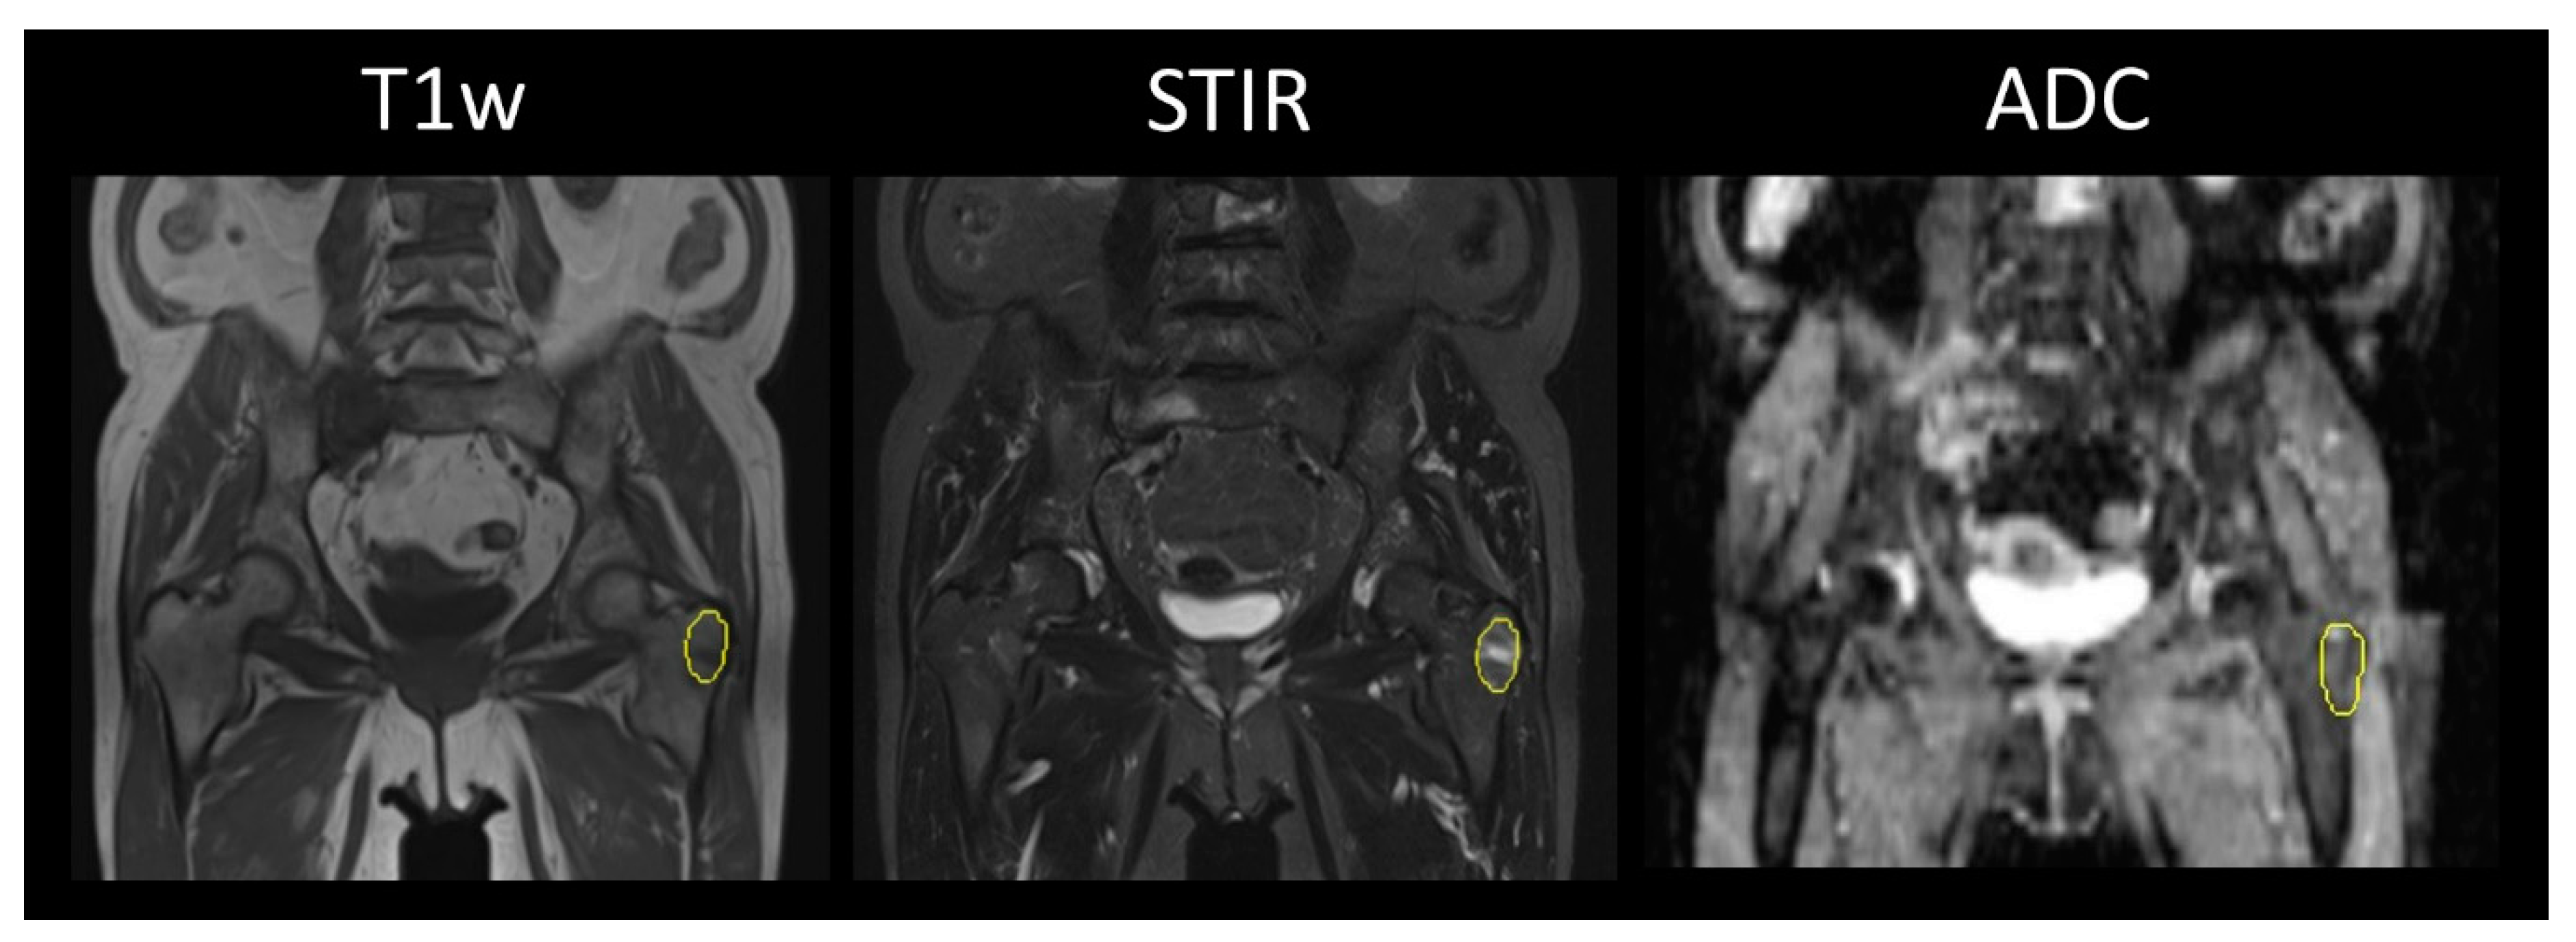

2.3. Image Analysis